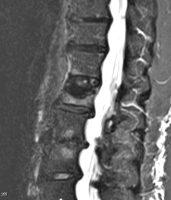

Möglichkeiten der direkten Zementinjektionstechnik bei Wirbelkörperfrakturen - Drei Fallbeschreibungen der Radiofrequenz-Kyphoplastie (RFK) mit ultrahochvikösem Knochenzement